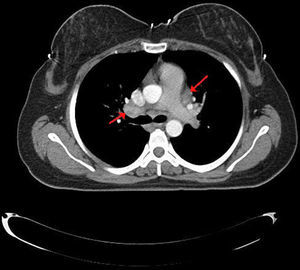

Case presentationA 35-year-old female patient was admitted to our Rheumatology clinic with complaints of pain and swelling in the ankle joint, morning stiffness, fatigue, dry cough, and palpitations. Physical examination revealed findings related with right ankle arthritis, growth and tenderness of the thyroid gland in palpation and tachycardia in cardiac auscultation. As for thyroid function tests; we determined FT3: 14.27pg/ml (normal 2.0–4.4pg/ml), FT4: 5.25ng/dl (normal 0.93–1.7ng/dl), TSH: 0.01ng/dl (normal 0.27–4.2ng/dl), anti-thyroglobulin: 164.7IU/ml (normal 0–115IU/ml), anti-TPO: 7.10IU/ml (normal 0–34IU/ml), TSH receptor antibody: 12.77IU/L (normal<1.22IU/L). Serum ACE level was found as 89 (normal <35). In the serological tests; ANA, ANCA, anti-CCP, RF were found to be negative. Thoracic CT revealed mediastinal and bilateral hilar lymphadenopathy (Fig. 1). The chest disease specialist was contacted, endobronchial ultrasound (EBUS) guided biopsy was performed. Histopathological evaluation showed non-caseating granulomas, thus sarcoidosis was considered in the patient. Thyroid ultrasonography showed the increased size of the thyroid gland, with heterogeneous and coarse parenchyma, which appeared to be related with Graves’ disease. Diffusely increased uptake of radioactive iodine was found in thyroid scintigraphy. The patient was diagnosed with sarcoidosis and Graves’ disease based on clinical, laboratory, radiological and histological data. Moderate dose of a corticosteroid (40mg/day) and propylthiouracil 3×1/day were initiated to the patient. At the 6th month of clinical follow-up, thyroid function tests were observed to be normalized, palpitations and complaints of locomotor system were found to be decreased. Control thorax CT showed significant regression in terms of mediastinal and hilar lymphadenopathy.